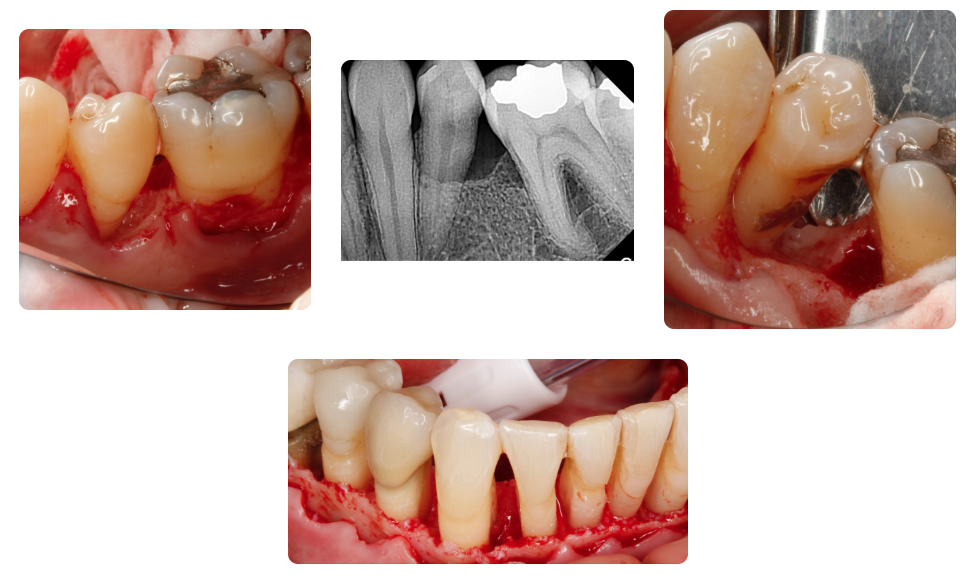

This course is designed for clinicians who wish to sharpen and expand their surgical skillset to predictably and consistently improve long term implant success through optimization of the hard & soft tissue from the moment the tooth is being extracted, through implant site preparation.

The full spectrum of hard and soft tissue optimization surgical techniques will be discussed and presented to capitalize on the naturally occurring wound healing physiology of the fresh socket to maximize bone growth and soft tissue management.

- Comprehend the indications, guidelines and surgical steps for different methods of bone grafting.

- Have a better understanding of the anatomy and the biology of wound healing and bone graft maturation.

- Improve their skills in diagnosis, prevention, and management of complications associated with hard and soft tissue grafting.